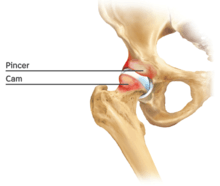

Cam-type femoroacetabular impingement

Cam impingement is created by the abnormal development of the femoral head-neck junction causing what has previously been described as a 'pistol-grip deformity'. This type of deformity is characterised by varying amounts of abnormal bone on the anterior and superior femoral neck at the head-neck junction (see fig. 6). The head-neck junction is at the base of the ball of the hip, where it joins the short neck, which in turn carries on downwards into the femur, or thighbone, itself. A bony protrusion or bump at the head-neck junction has been likened to a cam, an eccentric part of a rotating device. This leads to joint damage as a result of the non-spherical femoral head being forced into the acetabulum mainly with flexion and/or internal rotation. This may impart compression and shear forces to the articular cartilage, and may lead to labral tears and peeling away of the articular cartilage from the underlying bone, so-called cartilage delamination (see fig. 8).[9][10]

Standard arthroscopic treatment of symptomatic cam FAI involves debridement (resection) or repair of any labral [10] and chondral injuries [11] in the central compartment of the hip, and subsequent reshaping of the head-neck junction of the upper femur (osteochondroplasty) in the peripheral compartment [12][13] using high-speed motorised burrs that are similar in design to a dentist's drill (see fig. 9).

Pincer-type femoroacetabular impingement

In contrast, pincer impingement is a result of an abnormality on the acetabular side of the hip joint.[2] The acetabulum may either have a more posterior orientation than normal, otherwise known as acetabular retroversion, or there may be extra bone around the rim. This results in contact of the femoral neck against the labrum and rim of the acetabulum during hip movement earlier than might otherwise be the case. Repeated contact between the femoral neck and the edge of the acetabulum may lead to damage to the labrum and adjacent articular cartilage. Bone formation, or ossification within the labrum may be commonly seen as a result of this repeated contact. It is thought that this type of impingement may also predispose to the development of osteoarthritis.

The goal of the arthroscopic treatment of pincer impingement is to reduce the acetabular over coverage of the hip. Methods to reduce this over coverage of the ball by the socket include labral detachment or peel back, acetabular rim trimming using burrs, often reattaching the labrum with anchors at the end of the procedure. With the exception of cases of severe global over coverage of the hip, or situations in which the existing labrum has turned to bone (or ossified), excessive acetabular rim resection should be avoided in order to prevent iatrogenic increases in hip joint contact pressures.[14]